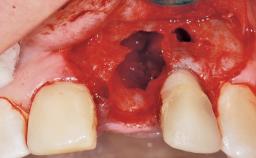

Late Flapless Placement of an Implant in a Maxillary Left Central Incisor Site

A 39-year-old male patient presented with a chief complaint of discomfort and gingival discoloration around his maxillary left central incisor. He was in good general health and was a non-smoker. His past dental history was significant because of the traumatic fracture of tooth 21 in a sporting accident at age 13. Initial dental treatment included endodontic therapy and a full-coverage restoration. The patient became symptomatic 5 years later, when structural failure of the tooth resulted in the dislodgment of the crown. Endodontic retreatment, apical surgery, and post-and-core restoration were performed.

Bone Volume Horizontally and vertically sufficient Horizontally deficient Deficient vertically or deficient vertically AND horizontally

Bone Volume Deficient horizontally, requiring prior grafting

Bone Augmentation Horizontal|Staged